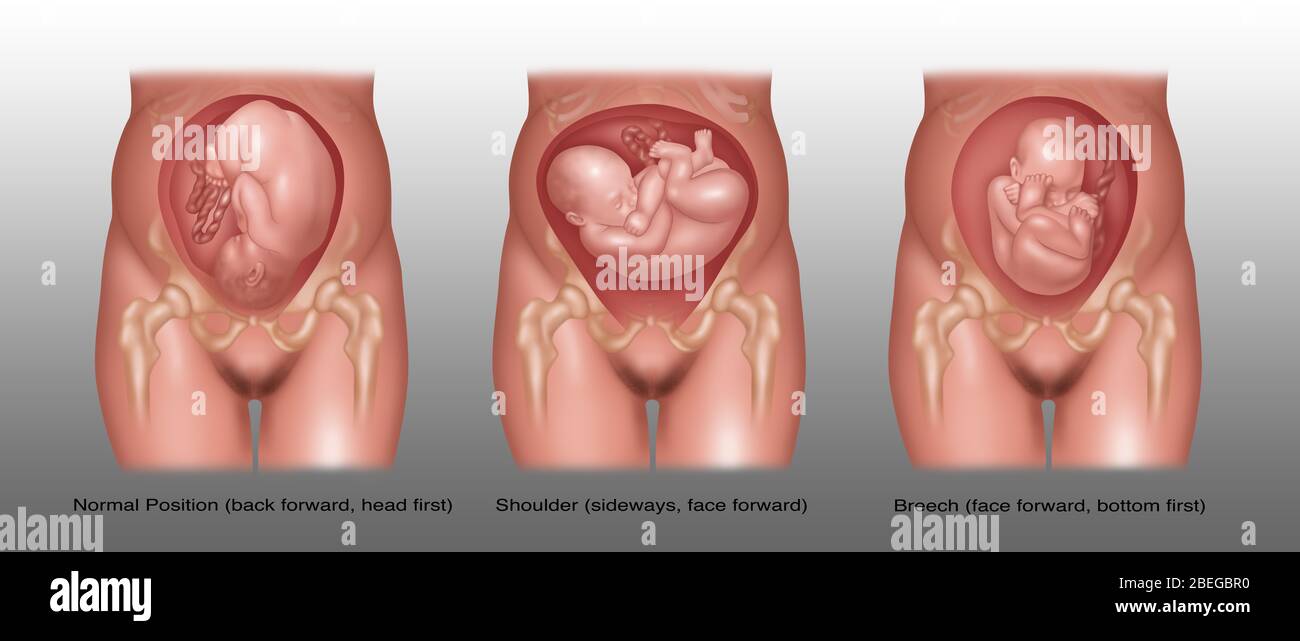

Fetus Positions in Uterus, Illustration Stock Photohttps://www.alamy.com/image-license-details/?v=1https://www.alamy.com/fetus-positions-in-uterus-illustration-image353173031.html

Fetus Positions in Uterus, Illustration Stock Photohttps://www.alamy.com/image-license-details/?v=1https://www.alamy.com/fetus-positions-in-uterus-illustration-image353173031.htmlRF2BEGBPF–Fetus Positions in Uterus, Illustration

Fetus Positions in Uterus, Illustration Stock Photohttps://www.alamy.com/image-license-details/?v=1https://www.alamy.com/fetus-positions-in-uterus-illustration-image353173074.html

Fetus Positions in Uterus, Illustration Stock Photohttps://www.alamy.com/image-license-details/?v=1https://www.alamy.com/fetus-positions-in-uterus-illustration-image353173074.htmlRF2BEGBT2–Fetus Positions in Uterus, Illustration

Fetus Positions in Uterus, Illustration Stock Photohttps://www.alamy.com/image-license-details/?v=1https://www.alamy.com/fetus-positions-in-uterus-illustration-image353173049.html

Fetus Positions in Uterus, Illustration Stock Photohttps://www.alamy.com/image-license-details/?v=1https://www.alamy.com/fetus-positions-in-uterus-illustration-image353173049.htmlRF2BEGBR5–Fetus Positions in Uterus, Illustration

Fetus Positions in Uterus, Illustration Stock Photohttps://www.alamy.com/image-license-details/?v=1https://www.alamy.com/fetus-positions-in-uterus-illustration-image353173070.html

Fetus Positions in Uterus, Illustration Stock Photohttps://www.alamy.com/image-license-details/?v=1https://www.alamy.com/fetus-positions-in-uterus-illustration-image353173070.htmlRF2BEGBRX–Fetus Positions in Uterus, Illustration

Fetus Positions in Uterus, Illustration Stock Photohttps://www.alamy.com/image-license-details/?v=1https://www.alamy.com/fetus-positions-in-uterus-illustration-image353173044.html

Fetus Positions in Uterus, Illustration Stock Photohttps://www.alamy.com/image-license-details/?v=1https://www.alamy.com/fetus-positions-in-uterus-illustration-image353173044.htmlRF2BEGBR0–Fetus Positions in Uterus, Illustration